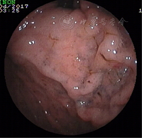

辅助检查:便常规+潜血:潜血阳性;血常规、凝血功能正常;难辨梭菌抗原及毒素检测阴性;血生化白蛋白30.4 g/L、钾3.02 mmol/L,余无明显异常;甲状腺功能T3、T4正常、促甲状腺激素(TSH)0.38 mU/L;结核干扰素测定正常;血清肿瘤标志物正常;血沉2 mm/1 h;CRP正常;类风湿因子(RF)101.9 kU/L;免疫球蛋白IgA、IgM、IgG正常,补体C3 0.672 g/L,补体C4 0.157 g/L;IgG亚类测定四项正常;抗核抗体(ANA)阴性;抗中性粒细胞胞浆抗体(ANCA)阴性;狼疮五项阴性;狼疮抗凝因子试验正常;心磷脂抗体正常;抗着丝点抗体阴性;腹部超声未见异常;甲状腺超声:甲状腺右叶实性结节;胸部CT:双侧胸腔少量积液;胃镜示胃底、胃体、胃窦弥漫性大小不等结节状息肉样隆起(图3),部分融合,表面充血水肿,以胃体、胃窦为重,胃底部可见黏膜下黑褐色素斑沉着(图4),十二指肠降部见散在小息肉样隆起;快速尿素酶法检测幽门螺杆菌阴性;胃窦、胃底、十二指肠降部取病理示慢性炎症;肠镜示回肠末端、盲肠、结肠、直肠广泛充血性息肉样隆起(图5),回肠、近端结肠息肉较小(直径0.1~0.2 cm),远端结肠、直肠息肉较大(直径0.2~0.4 cm)。病理示回肠慢性炎症,伴黏膜糜烂;盲肠增生性息肉,慢性炎症;直肠增生性息肉,慢性炎症,伴腺体囊状扩张。诊断:CCS。